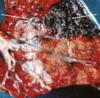

Progressive ethmoid haematoma endoscopy - reddening = haemorrhage

Paranasal sinus cysts in foals and young horses -> face + teeth distortion